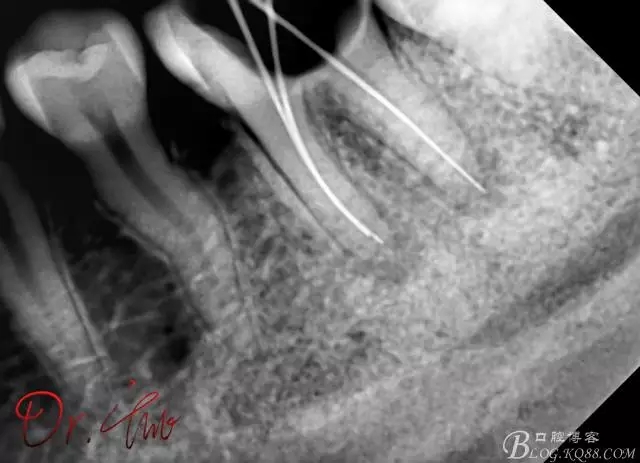

試主尖,近中頰側(cè)試主尖,此時手用銼02錐度的已擴到30號,可以明顯感覺到臺階位置,挫預彎后找好正確位置可順利到達根尖,但是機用銼就是下不去,也是郁悶

試主尖,在30號02錐度K挫到達根尖后,用02錐度牙膠尖找準位置,進行試尖

最后根充,明顯可看到臺階位置,期待預后效果